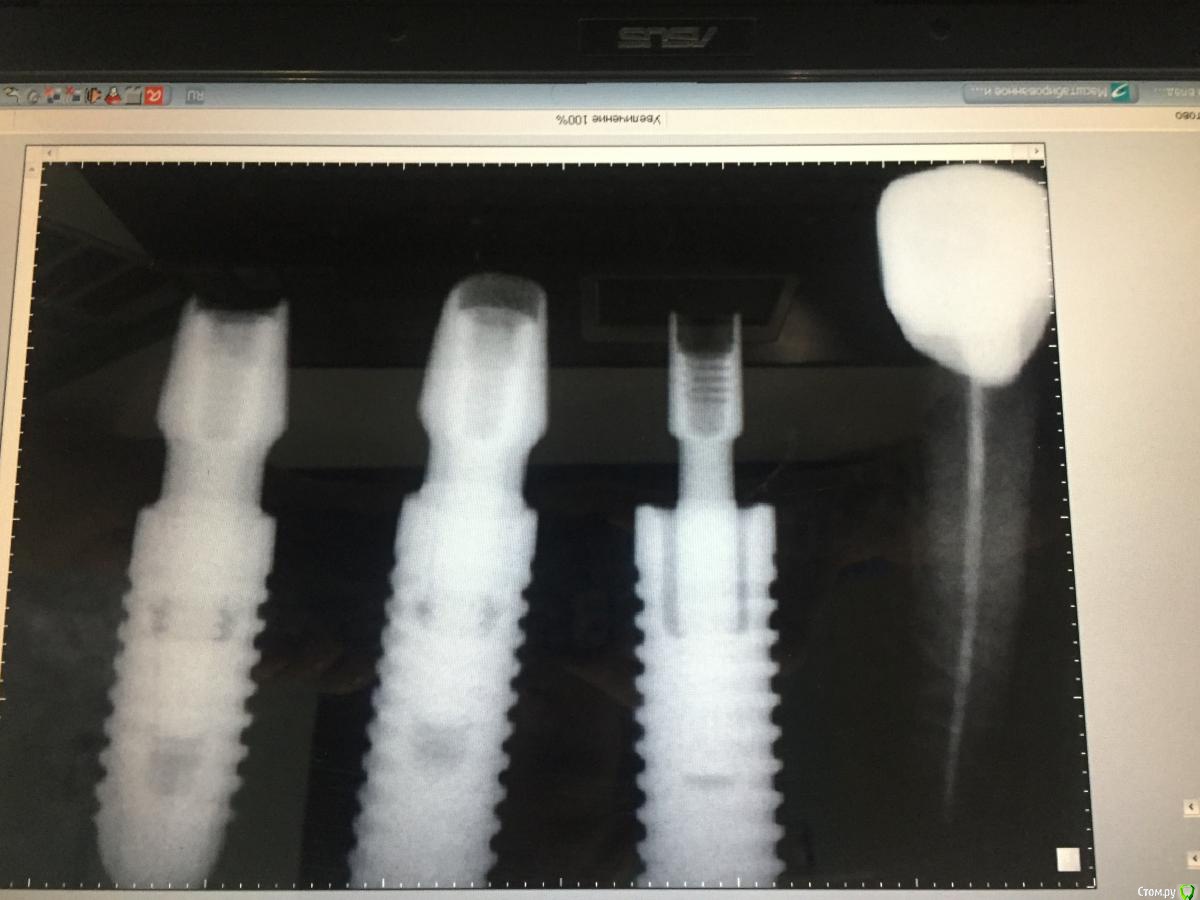

Romanson Опубликовано 9 февраля, 2019 Поделиться Опубликовано 9 февраля, 2019 Приветствую уважаемых участников форума! Помогите определить, что за производитель у имплантанта.http://i.piccy.info/i9/a40e67feedddeda0a63817be1e282f86/1549698867/56072/1294807/radio_exam.jpg Ссылка на комментарий

АнтонТЛТ Опубликовано 9 февраля, 2019 Поделиться Опубликовано 9 февраля, 2019 На Нобель селект похоже 1 Ссылка на комментарий

Lodkin666 Опубликовано 28 февраля, 2020 Поделиться Опубликовано 28 февраля, 2020 Коллеги, помогите. Со слов пациентки импланты установлены в КДЦ МГМСУ более 15 лет назад профессором Ивановым, требуется перепротезирование. Что это? Не Израиль, не Корея точно. Внутри шестигранник, более длинный чем у Израильских винтов. Ссылка на комментарий

red_butler Опубликовано 28 февраля, 2020 Поделиться Опубликовано 28 февраля, 2020 Коллеги, помогите. Со слов пациентки импланты установлены в КДЦ МГМСУ более 15 лет назад профессором Ивановым, требуется перепротезирование. Что это? Не Израиль, не Корея точно. Внутри шестигранник, более длинный чем у Израильских винтов.Это ЛИКо, производителя больше нет, гуглите НИКо и ИРИС, нико должны подойти 1 Ссылка на комментарий

КДБ Опубликовано 29 февраля, 2020 Поделиться Опубликовано 29 февраля, 2020 Добрый день.Лет 10 назад плотно сидели на ЛИКО,потом НИКО...Дизайн резьбы вроде не тот...Хотя кто знает.Менялась их линейка-стандарт,стандарт плюс(из неагрессивной линейки).Если ЛИКО,то платформ 2 е.На 4 и 5 мм 1 Ссылка на комментарий